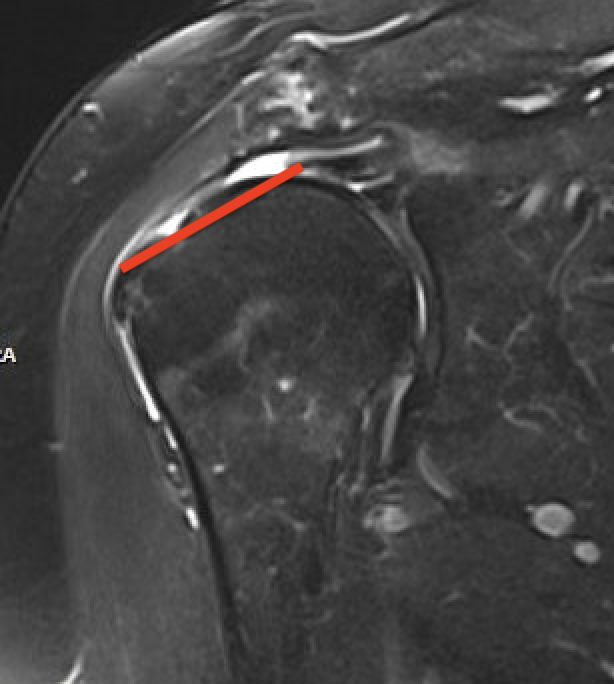

Full thickness rotator cuff tears

Partial bursal sided tear Partial articular sided tears

Small full thickness rotator cuff tear of supraspinatus - retracted to footprint

Large full thickness tear of supraspinatus and infraspinatus tendon - retracted to midhumeral head

Massive rotator cuff tear of the supraspinatus and infraspinatus tendon - retracted to glenoid

Measure tear in the coronal and sagittal plane